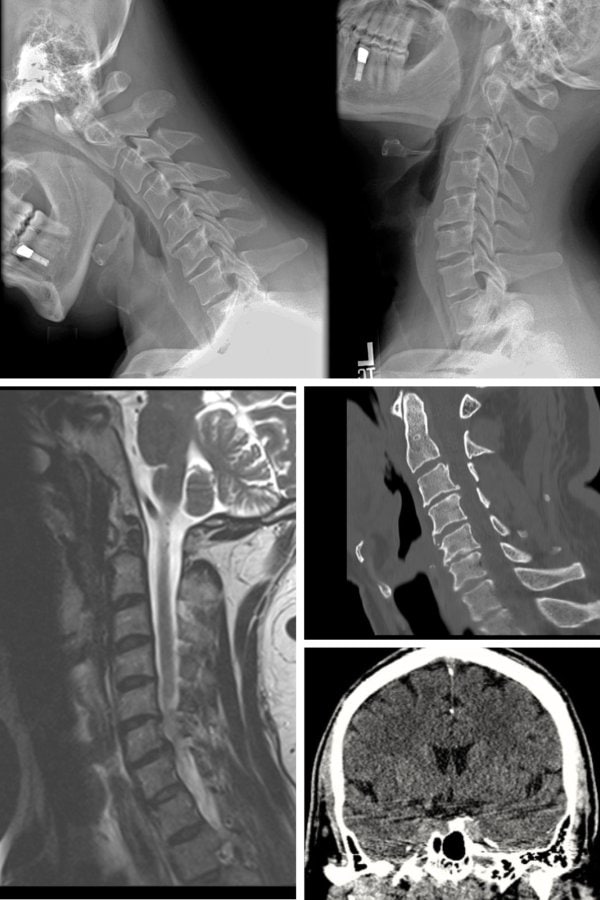

These symptoms often indicate nerve involvement from herniated discs or nerve root compression. Dr. Kovacs’ MRI interpretation expertise ensures accurate diagnosis and appropriate treatment.

✔ MRI-based analysis of disc injuries

✔ Age-dating of herniations when applicable

✔ Identification of ligament injuries (AOMSI)